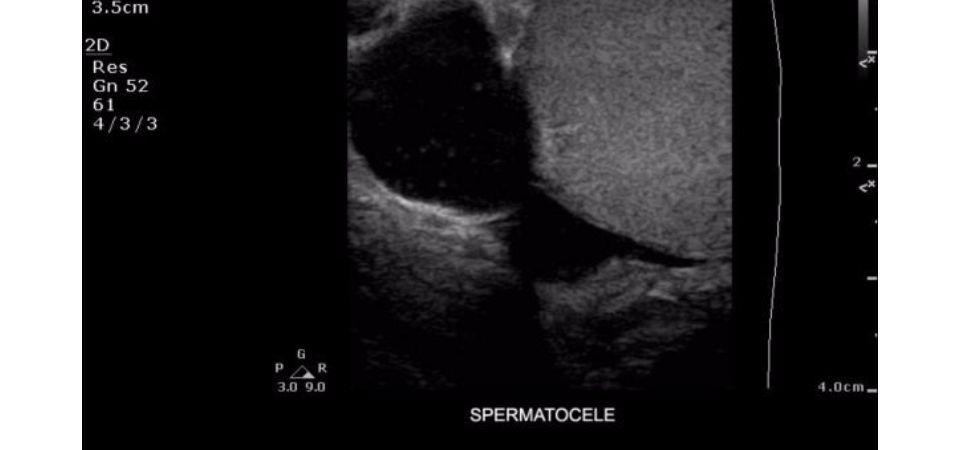

Philips ClearVue 350 представляет собой современную ультразвуковую систему, которая сочетает в себе передовые технологии визуализации, удобство использования и широкие диагностические возможности. Благодаря инновационным решениям и продуманной эргономике, система обеспечивает высокую эффективность работы медицинского персонала.

Технология XRES: Фирменная технология обработки изображений Philips в сочетании с предустановленными настройками датчиков значительно повышает качество визуализации и достоверность диагностики.

• Широкополосное формирование ультразвукового луча с усовершенствованной обработкой сигнала для точной дифференциации тканей

• Режим тканевой гармоники для подавления артефактов при сохранении высокого разрешения

• Урология